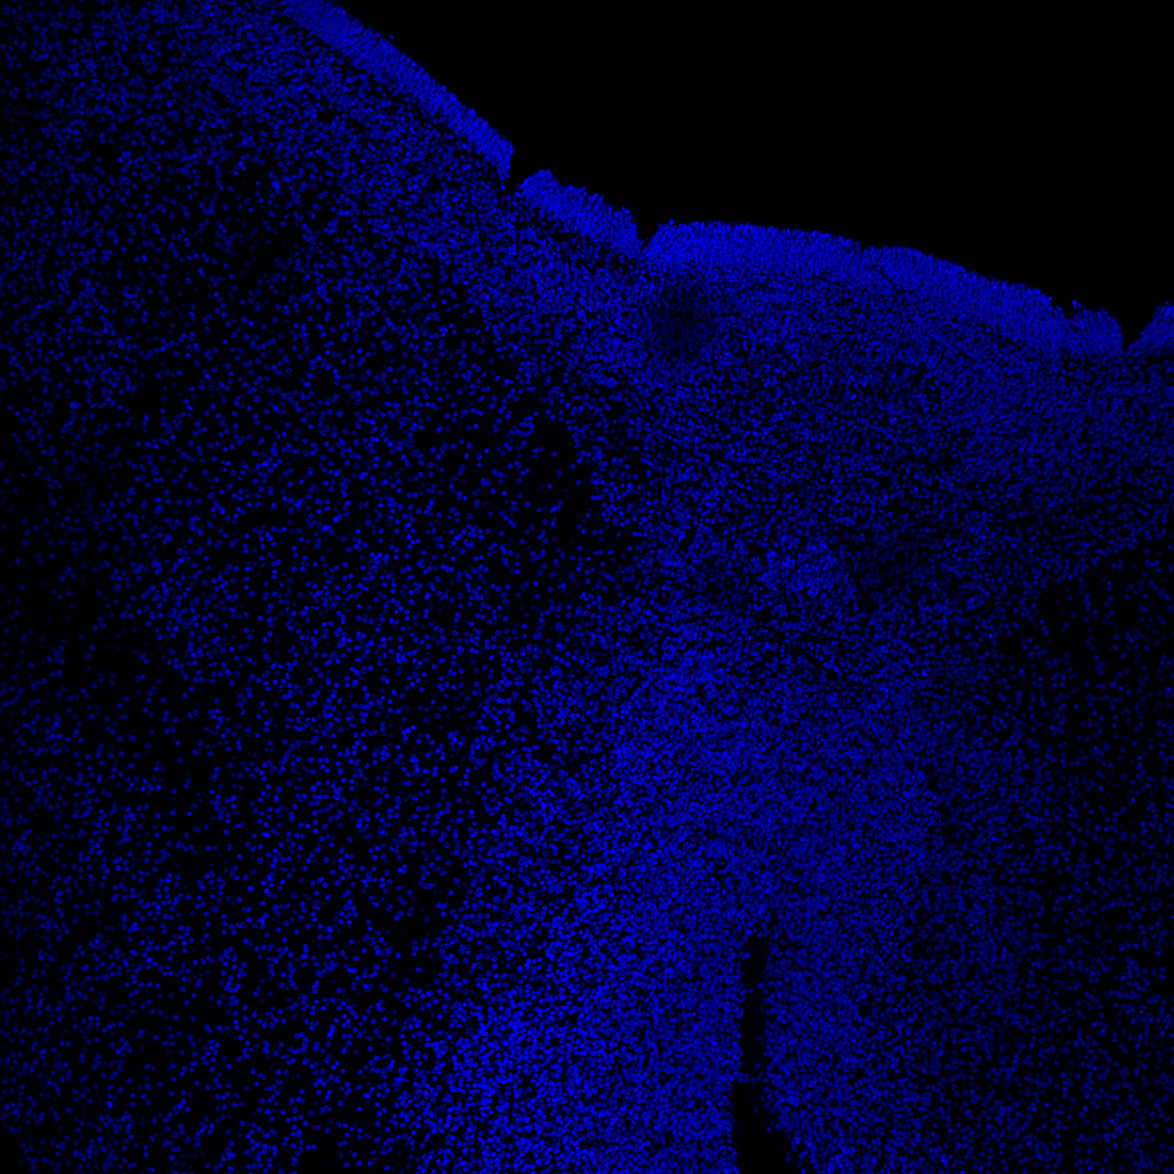

6PCW

DAPI

6PCW human midbrain